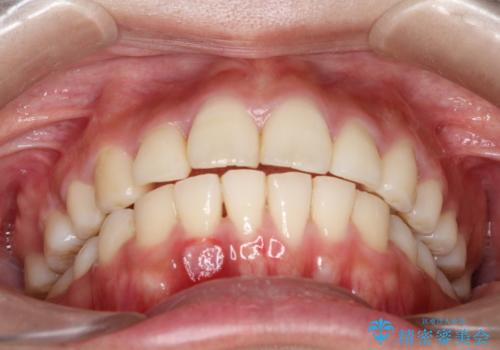

上下の前歯の距離が近くなり、前歯で咬みやすくなり、審美的にも改善できました。